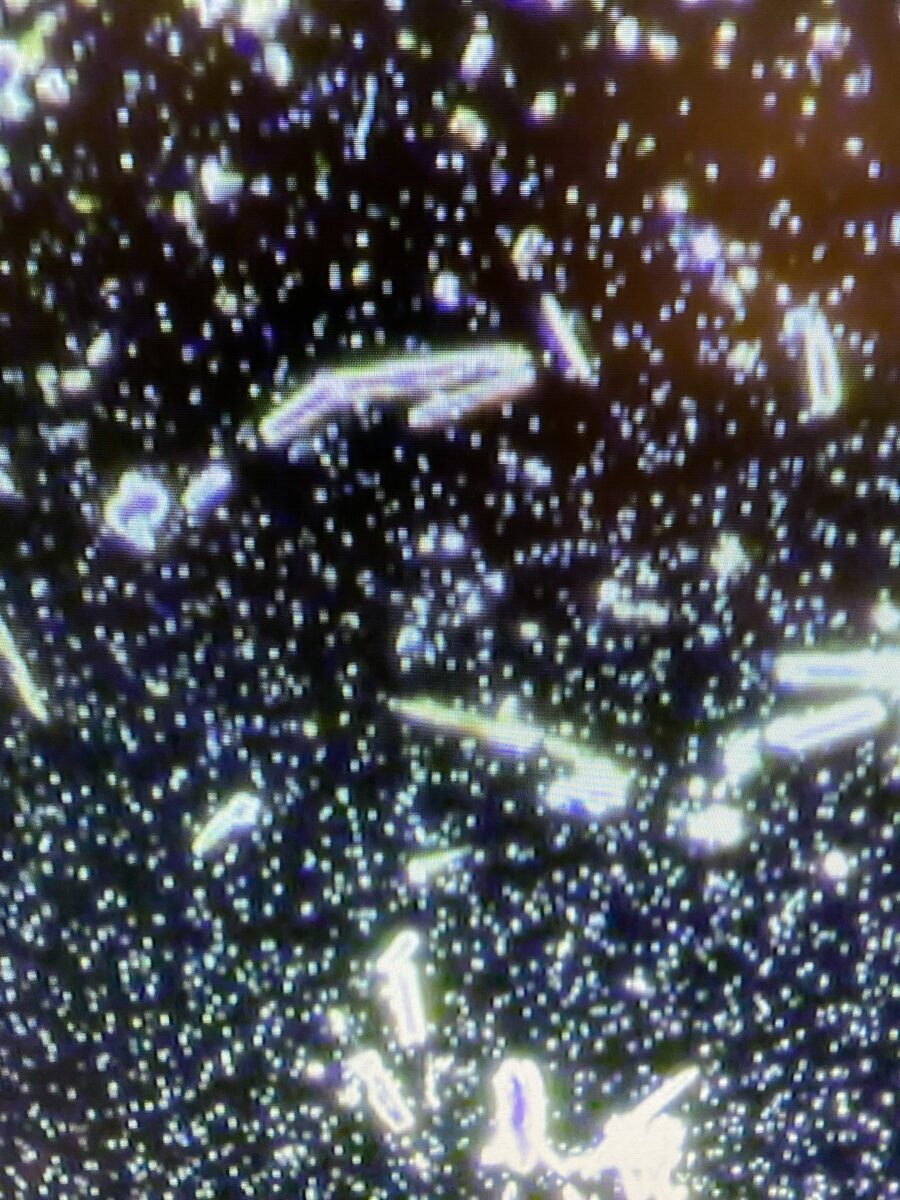

Our latest finding possibly show what has been suspected to be graphene oxide; these are very unnatural formation (rod shape crystals) that should not appear in the living blood.

We are not biochemist and do not have the technical abilities to test those but some other research and scientist did.

A recent investigation by Dr Ricardo Delgado Martin and the technical report by Dr Pablo Campra ‘Detection of graphene in COVID vaccines by micro-Raman spectroscopy’ claim that the COVID-19 vaccines contain graphene.

As reported by CORDIS in 2018, a team of researchers has proven that graphene is able to convert electronic signals into signals in the terahertz range, with trillions of cycles per second.

The silicon-based electronic components we use today generate clock speeds in the GHz range, where 1 GHz is equal to 1 000 million cycles per second. The scientists showed that graphene can convert signals with these frequencies into signals with frequencies that are thousands of times higher than those created by silicon.

Graphene is therefore able to absorb radiation, meaning that, if contained in a vaccine, it would be highly toxic and harmful to human health.